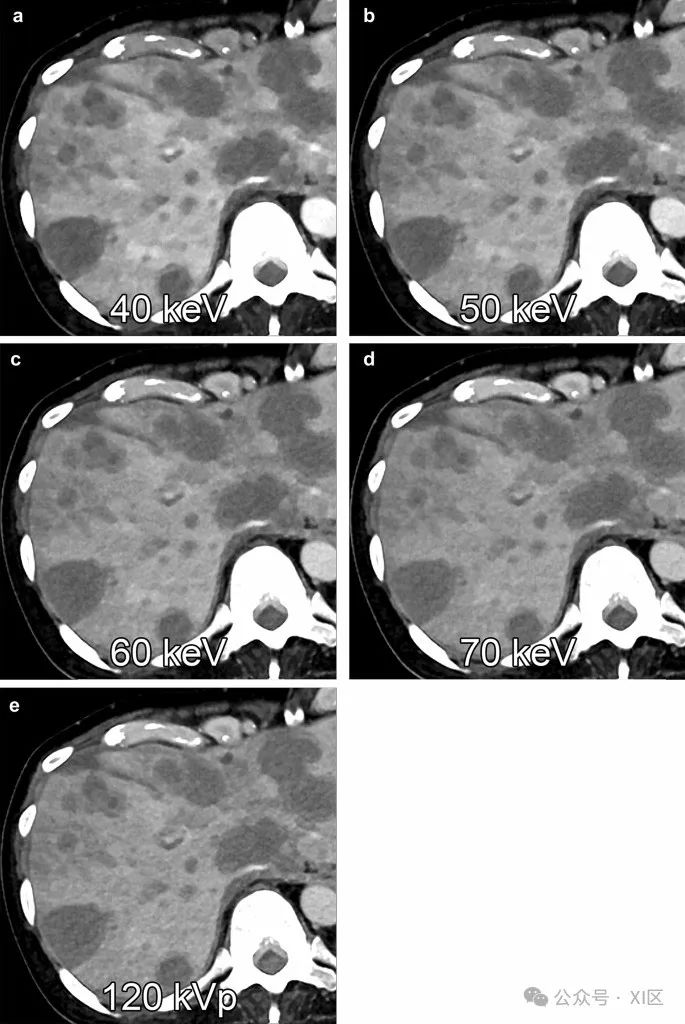

肝转移是最常见的肝癌类型,大多数病例具有低血管特征。与常规单能量CT相比,光子计数CT的虚拟单色图像显示出降低的图像噪声,在较低的keV水平上提高了低血管肝转移的显著性,尤其是高体重指数的患者比常规CT受益更多(图6)。

图6 多发性胰腺癌转移性肝肿瘤在虚拟单色图像上显示,分别为40 keV(A)、50 keV(B)、60 keV(C)、70 keV(D)和用光子计数CT在120 kVp时获得的多色图像(即T3D)(E)在门静脉优势期期间。肝转移和肝实质之间的对比噪声比分别为14.6、11.9、9.8、8.5和7.4。肝脂肪变性